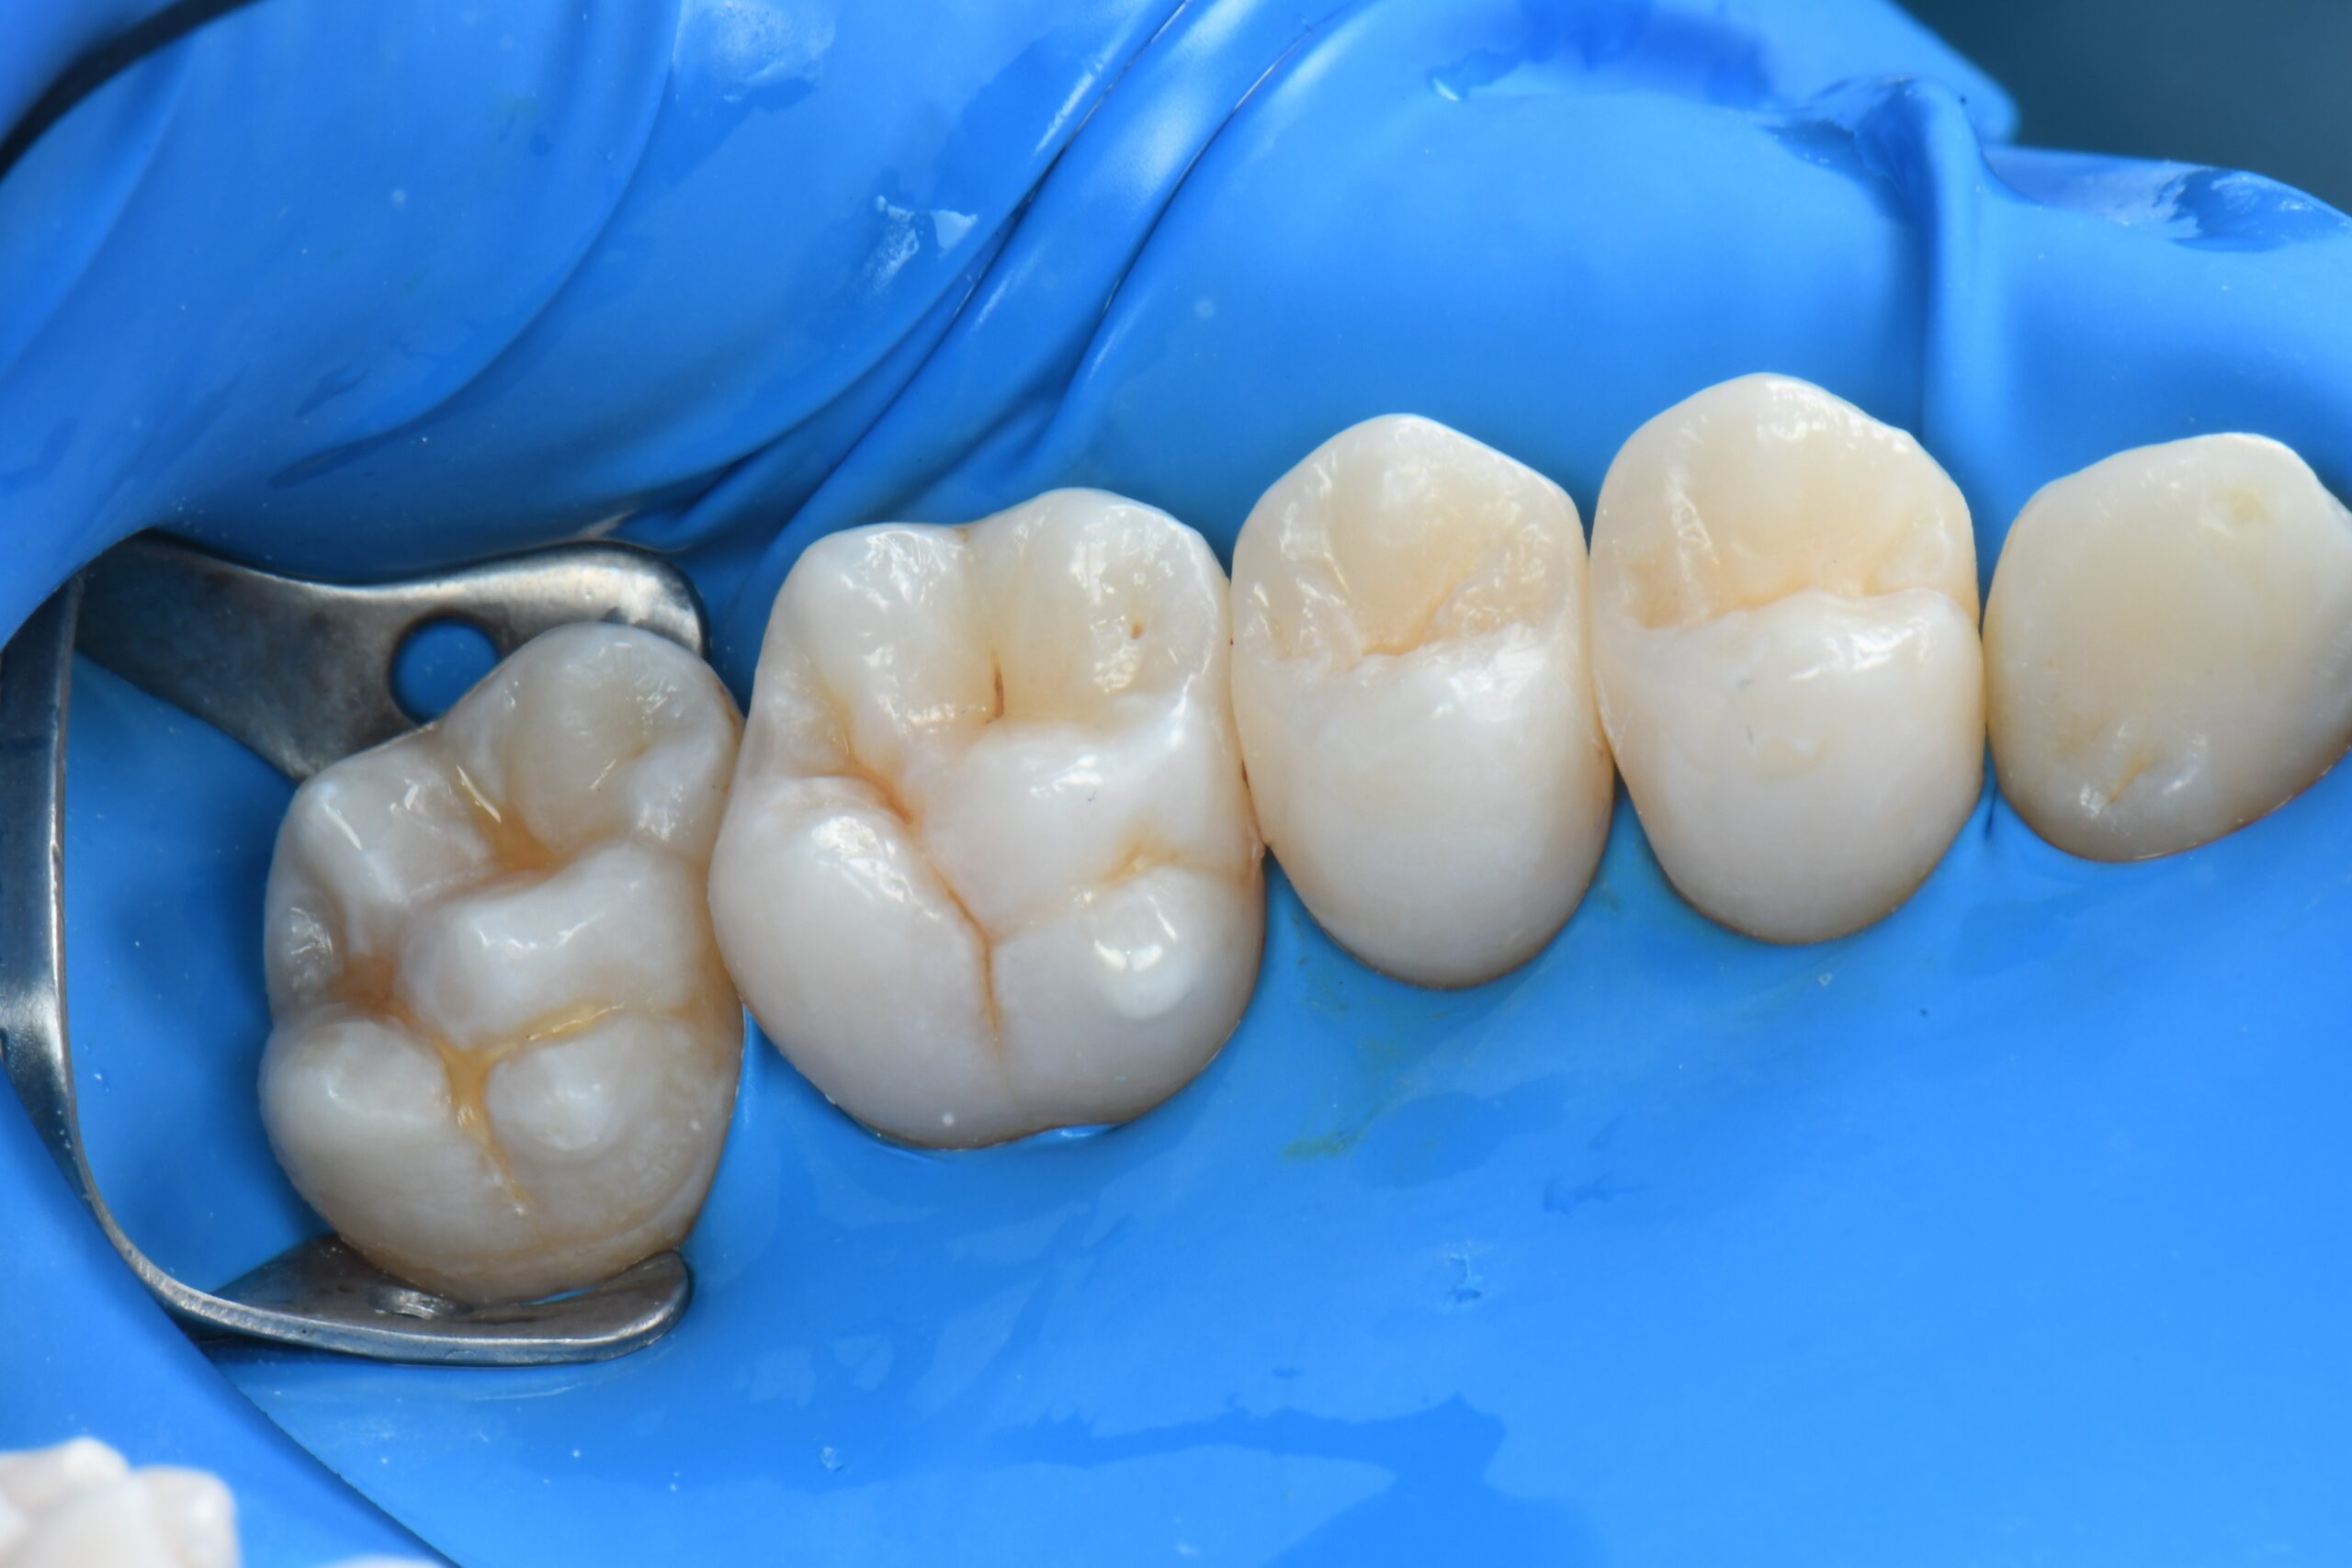

Close-up of four molar teeth isolated with a blue dental dam and metal clamp on the leftmost tooth

After a quick finishing phase, the restorations are polished with rubber burs and a polishing brush.